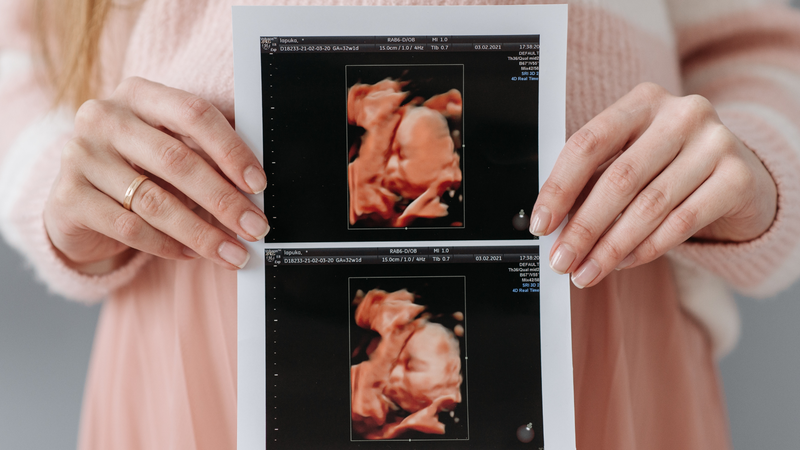

Ngay từ khi biết tin mang thai, nhiều mẹ đã bắt đầu suy đoán xem bé là “công chúa” hay “hoàng tử”. Dù việc xác định giới tính thai nhi chính xác cần đến siêu âm hoặc xét nghiệm, nhưng những quan sát từ cảm giác trong thai kỳ vẫn thường được chia sẻ như một “bí kíp dân gian”. Vậy sự khác nhau giữa mang thai con trai và con gái có gì thú vị? Hãy cùng khám phá qua các phần dưới đây.

Trong suốt thai kỳ, nhiều mẹ bầu hay người thân thường cố gắng “đoán” giới tính thai nhi dựa trên hình dáng bụng, sở thích ăn uống hoặc tình trạng da dẻ. Một số ý kiến cho rằng bụng bầu thấp và nhọn là dấu hiệu mang thai con trai, trong khi bụng cao và tròn nghiêng về mang thai bé gái. Ngoài ra, sở thích ăn mặn, ngọt hay tình trạng da mặt cũng được xem là “manh mối”. Tuy nhiên, những dấu hiệu này chủ yếu là kinh nghiệm truyền miệng, hiện chưa có bằng chứng y học xác thực.

Các dấu hiệu kể trên chủ yếu mang tính tham khảo, chưa thể dùng làm cơ sở để xác định giới tính thai nhi. Việc chẩn đoán chính xác vẫn cần đến các phương pháp y học như siêu âm đúng thời điểm hoặc xét nghiệm phân tích ADN trong thai kỳ.